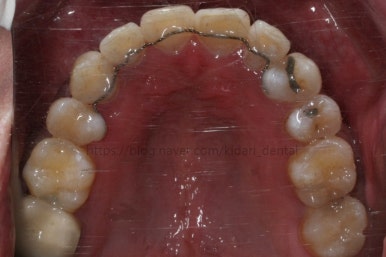

부산치아교정 키다리아저씨치과에 처음 내원 당시의 입안 모습입니다.

여러 가지 문제점이 있는데 하나씩 살펴볼게요.

치열이 많이 삐뚤하네요.

많이 삐뚠 상태에서 장기간 사용하다 보면 안좋은 방향으로 치아가 힘을 받게 되고 마모나 치아 목부분 패임이 심해집니다.

양치가 힘들어요. 양치가 힘들다 보니 세게 닦게 되고 치아 손상은 더 심해져요. 25세의 나이였는데 나이에 비해서 치아나이가 굉장히 많은거죠.

화살표 부분에 원래 송곳니가 있어야 되는데 보이질 않네요. 결손치아일 수도 있고 매복치아일 수도 있겠어요.

왼쪽 위 어금니도 한 개가 없어서 빈공간이 약간 남아있어요.

왼쪽 아래 작은 어금니는 아래쪽으로 많이 꺼져있네요.

이런 경우 X-ray 도 면밀히 관찰해 줘야 합니다.